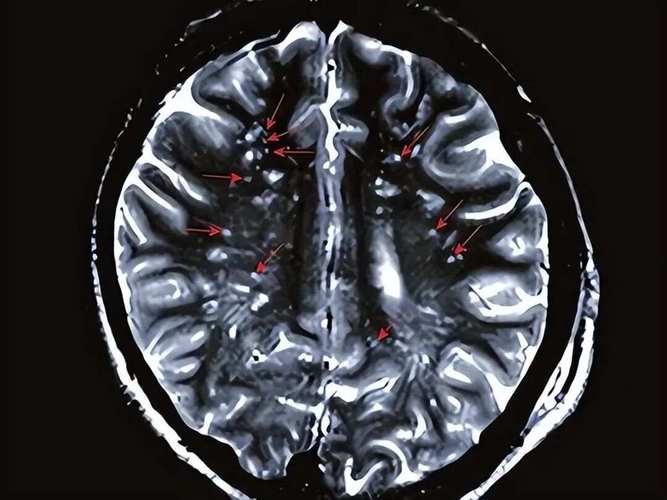

在CT或MRI上,陈旧性脑梗灶有非常典型的特征:

- CT(计算机断层扫描):表现为低密度(比周围正常脑组织颜色更深/更黑)的病灶,边界清晰,没有占位效应(不会压迫周围组织)。

- MRI(磁共振成像):这是诊断陈旧性脑梗最敏感的检查。

- T1加权像:表现为低信号。

- T2加权像和FLAIR像:表现为高信号(像一个小水泡或小空腔)。

- DWI(弥散加权成像):没有高信号,这是它与“急性期脑梗”最重要的区别,因为急性期细胞内水肿在DWI上是高信号的。

影像学特征

- CT:可能显示为一个小点状的低密度灶,但如果病灶太小或位于后颅窝(脑干、小脑),CT很容易漏诊。

- MRI:是诊断腔隙性脑梗的金标准,可以清晰地显示大脑深部的小点状、圆形或卵圆形的T2加权像高信号病灶。